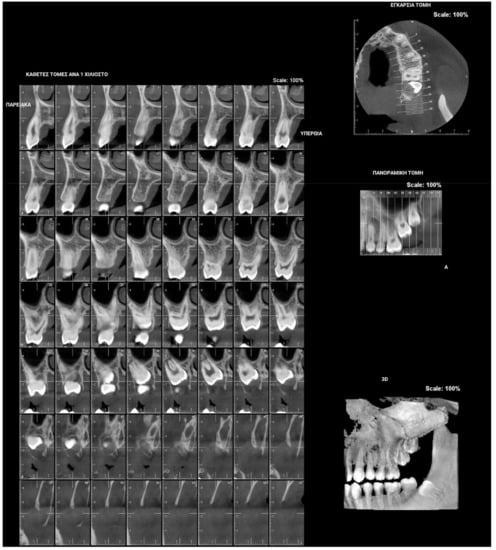

Figure 4.

Patient’s orthopantomography presenting Primary Failure of Eruption in all four dental quadrants.